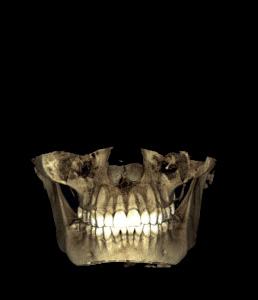

Planmeca ProFace™ is a unique 3D facial photo option available for all Planmeca’s 3D X-ray units. The upgraded unit produces a realistic 3D face photo in addition to maxillofacial radiography. Planmeca is the first to introduce this type of a concept. One imaging session generates both a 3D photo and a CBCT volume, or if required solely a 3D photo, in which case no radiation is emitted.

The 3D photo visualises soft tissue in relation to dentine and facial bones. As both a CBCT image and a 3D photo are generated in one imaging session, the patient position, facial expression, and muscle position remain unchanged – resulting in images that are perfectly compatible.

Careful pre-operative planning – where you can study the facial anatomy thoroughly using our Planmeca Romexis® software – facilitates accurate and detailed operations and enhances the aesthetic result.

Shows deviation to instantly see any changes Shows deviation to instantly see any changes Shows deviation to instantly see any changes

Shows deviation to instantly see any changes